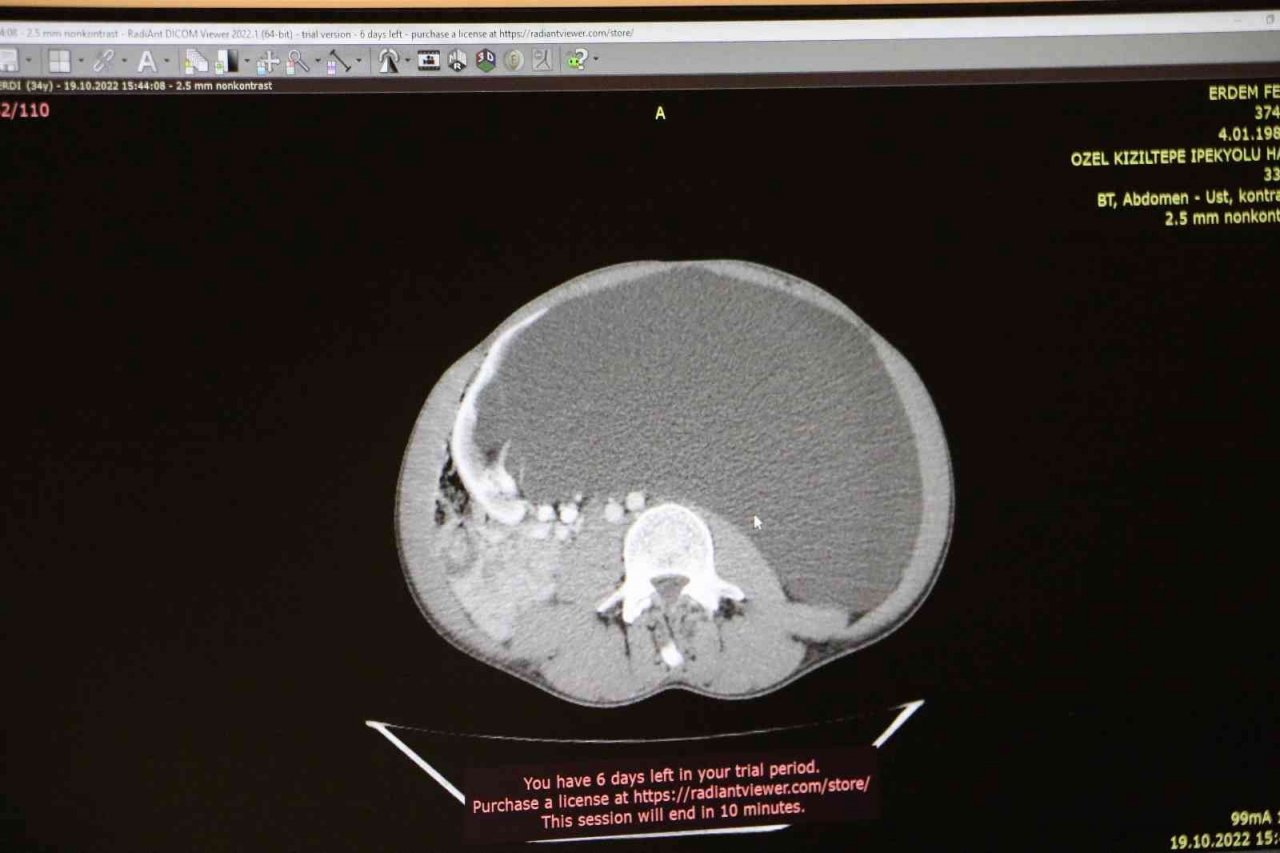

Mardin'de yaşayan 34 yaşındaki hasta, Diyarbakır'da Dicle Memorial Hastanesi'ne karnının sol tarafında şişlik, kilo kaybı ve sindirememe gibi şikayetlerle başvurdu. Genç hastanın böbreğinde 60 santimlik kisti alan doktorlar, hekimlik hayatları boyunca böylesini görmediklerini söyledi.

Erdem'e yapılan tetkikler sonrası böbreğinde 60 santimlik kist teşhisi koyulup ameliyat kararı aldıklarını söyleyen Dicle Memorial Hastanesi'nde görevli Op. Dr. Kemal Ertaş, "Kist her insanda görülebiliyor. Ama çoğu zaman küçük boyutlarda kalıp hiçbir belirti vermiyor ve tesadüfen saptanıyor. Belirti verenler genellikle büyük boyutlara ulaşan vakalardır. Ama bugüne kadar en sık gördüğüm böbrek kistindeki boyutlar 11-12 santimetre diyebilirim. Daha büyüğünü görmemiştim" ifadelerine yer verdi.

Ameliyat süreci hakkında bilgi veren Ertaş, Erdem'in böbreğinde çıkan kistin laparoskopik yöntemle alındığını belirterek, "Hasta nadir olarak gördüğümüz devasa boyutta bir kist ile karşımıza geldi. Hastamızın genç olması da ayrı ilginçlik arz ediyor. Hasta karın ağrısı ve karındaki şişkinlik şikayetiyle bize başvurdu. Yaptığımız tetkiklerde sol böbrekten kaynaklandığını düşündüğümüz, yaklaşık 60 santimetre boyutunda bir kist ile karşılaştık. Normalde bu sık gördüğümüz bir durum değil. Ben hekimlik hayatımda bugüne kadar böyle büyük boyutlarda bir kist görmedim. Literatüre baktığımızda da çok nadiren görüldüğünü fark ettik. Bu yüzden ehemmiyetle yaklaştık. Olabilecek diğer sebepleri dışladık ve bunun için bazı incelemeler yaptık. Bu incelemelerimizde bazen kanserler bu şekilde kendini gösterebiliyor veya karın içerisinde su birikmesi dediğimiz asit bu şekilde kendini gösterebiliyor. Bu sebepleri dışladıktan sonra böbrek kistine kanaat getirip hastamız için ameliyat kararı aldık. Normalde bu kadar büyük bir kisti açık olarak yapmak daha kabul edilebilir görünmekle birlikte bu hastada bunu kapalı bir şekilde laparoskopik yöntemle ameliyata almayı kararlaştırdık. Yaptığımız ameliyat ile güzel bir şekilde kapalı yöntemle kisti almayı başardık" diye konuştu.

Son olarak Erdem'in ameliyatını yaptıktan sonra vücudundan toplam 6 litre sıvı boşaltıldığını aktaran Ertaş, "Hastamızdaki kist o kadar devasa boyuttaydı ki bütün karın içi organları başka tarafa itip vücudun hemodinamisini bozmaya başlamıştı. Bu açıdan hastamızın ameliyat olması şarttı" ifadelerini kullandı.